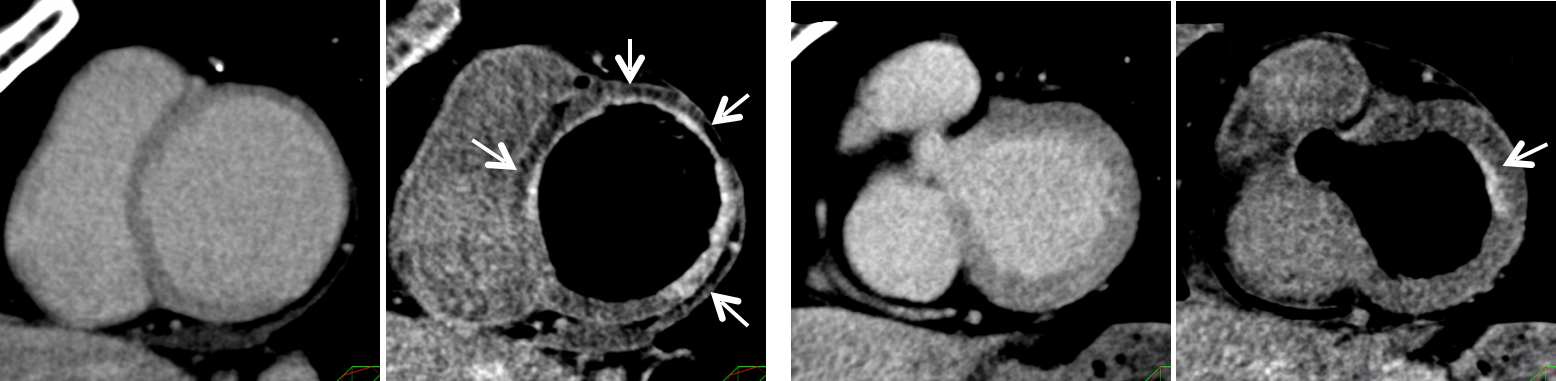

通常の画像(左)に比べ、石灰化(白い部分)を除去した画像(右)では血管狭窄の有無が明瞭に評価できます。

サブトラクション冠動脈CT

通常の画像(左)ではSTENT内の評価は困難ですが、サブトラクション画像(中央)によって末梢側に高度狭窄を疑われます(矢印)。カテーテル造影(右)でも同様の位置に高度狭窄病変を認めます(矢印)。

SMILIE

通常の遅延相の画像(左)では、心筋の異常を指摘するのは困難です。SMILIE(右)では、心筋梗塞となっている部分(矢印)が明瞭に描出されています。